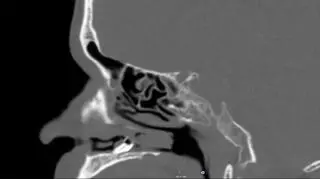

Tomograf komputerowy jamy nosowej mężczyzny (BMJ Case Reports)

Od ponad dwóch lat 59-latek cierpiał na dolegliwości związane z nosem. Miał zatkaną dziurkę nosa, wyciek dziwnej wydzieliny i pogarszał mu się węch. Kiedy początkowe próby leczenia nie poskutkowały, odwiedził oddział otorynolaryngologii (dziedziny medycyny zajmującej się rozpoznawaniem i leczeniem chorób ucha, nosa i gardła) w Szpitalu Uniwersyteckim w Aarhus w Danii. Tam tomografia komputerowa wykazała, że infekcja spowodowana była przez wyrośnięty w jamie nosowej ząb ektopowy.